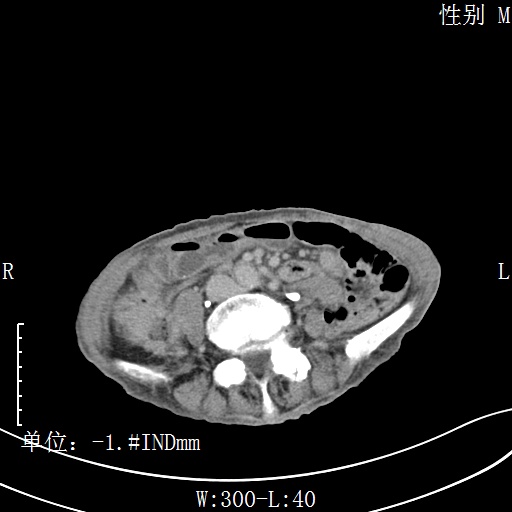

CT51080:肝脏病变,请各位高手会诊。

患者,男性、80岁。右上腹痛半年余,加重一周。无发热,WBC计数不高。CEA>1005ug/L, AFP:2.38ug/L

肝右叶占位,延迟强化,升结肠可见软组织密度影,管腔狭窄,不规则强化,考虑升结肠癌伴肝内转移。

升结肠占位、肝转移

症状病史不支持脓肿,病灶内壁不光整,壁厚薄不一,也不支持脓肿。所以还是考虑恶性肿瘤。

升结肠癌并肝转移。

考虑升结肠癌伴肝内转移